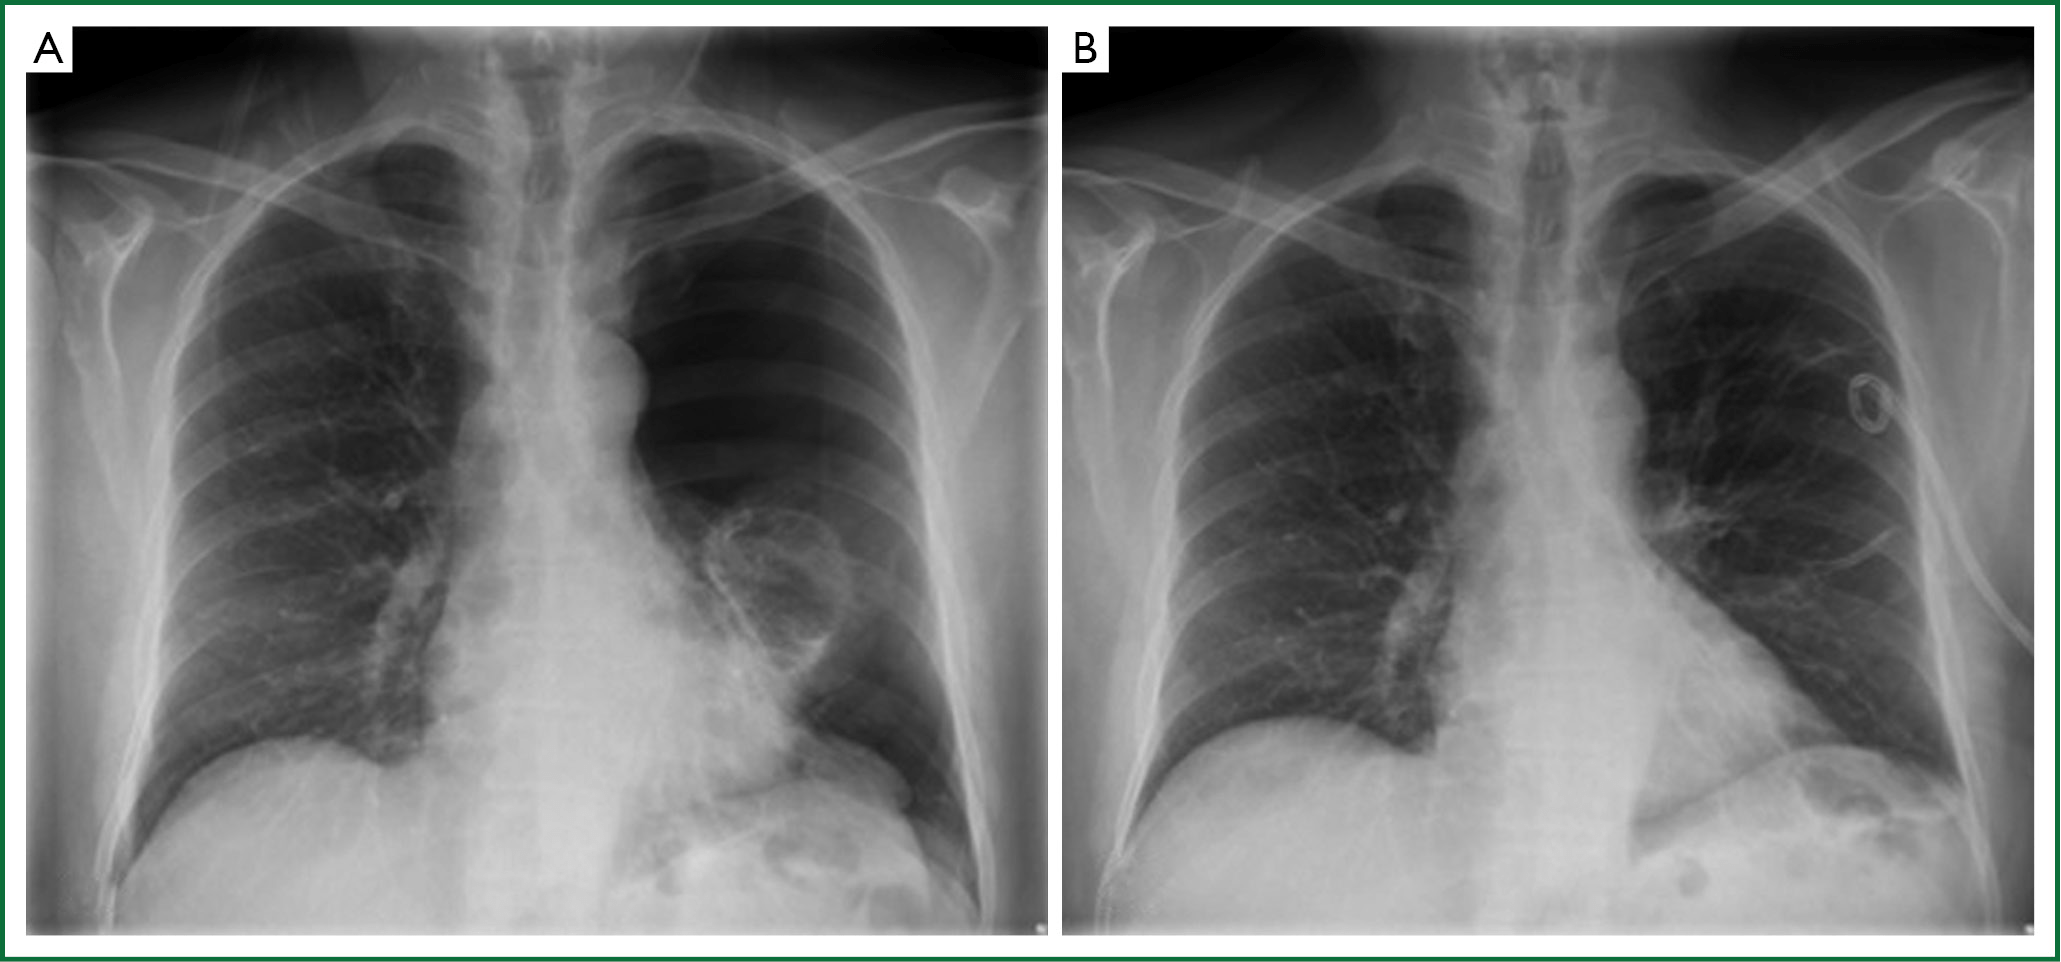

This x ray was performed to check the position of a chest drain used to treat a pneumothorax conventionally this x ray would be considered inadequate for diagnostic purposes as it does not include the costophrenic angles the chest drain position is shown clearly the image does not need to be repeated to include the costophrenic angles. Ng tube tip 10 cm distal to the gastro esophageal junction. This tutorial describes the correct anatomical location following placement of common tube devices seen on chest x rays. Insertion into trachea or bronchus pneumoniapulmonary contusionpulmonary laceration.